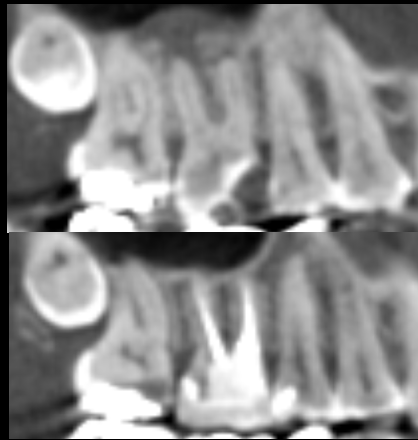

【池袋 歯医者】歯根嚢胞に対する歯根端切除術とは...